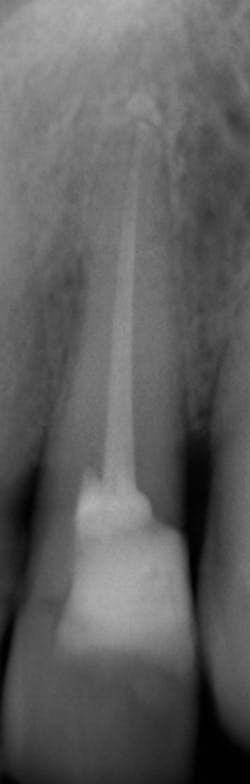

What’s unique about this system is that it uses nanotube technology to capture standard 2D images (figure 2) and gives you the option of taking a tomosynthesis image, which captures multiple images from several angles (figure 3). Images are compiled into a sliced volume and dissected into 0.5 mm or 0.1 mm slices that you can scroll through, rotate, enlarge, measure, and adjust. The system can “un-overlap” many teeth; this is convenient because with regular 2D x-rays, I had to retake the image at different angles and often with little success.

I see more complications and pathologies when using 3D tomosynthesis than I ever did with my old 2D images (figure 4). I can treat more because I can see more bone loss, interproximal caries, fractures, resorptions, abscesses, and more (figure 5).

In fact, twice today I was able to see something with Portray that wasn’t visible in the original 2D x-ray (figure 6). I don’t always take 2D images now, but I do when I think the case is straightforward or the patient has very little dental history. I often end up taking a tomosynthesis image just to be safe. With the 3D image I can scroll from buccal to lingual through the tooth and get much more data (figure 7). The new system has replaced my 2D PAs and bitewings.